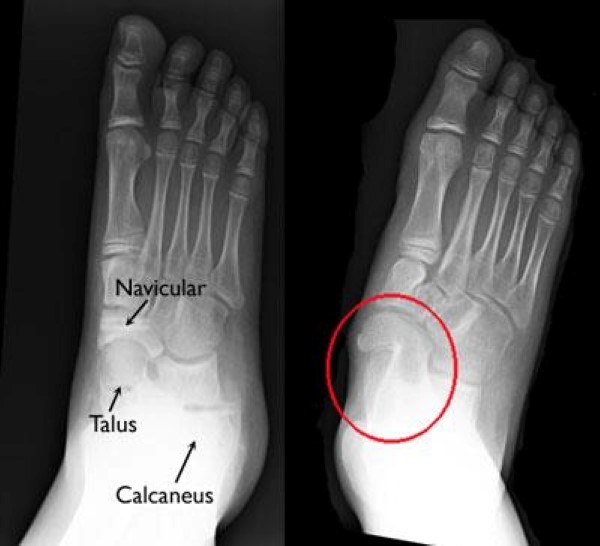

Fused ankle bones, Xray Stock Image M330/1360 Science Photo Library

Fused ankle bones, Xray Stock Image M330/1360 Science Photo Library Fused Bones Meaning spinal fusion is a surgical procedure used to correct problems with the small bones in the spine (vertebrae). arthrodesis is a surgical procedure that fuses two bones together. spinal fusion is a surgical procedure in which two or more vertebrae are permanently joined into one solid bone. spinal fusion is a surgical procedure that links bones. Fused Bones Meaning.